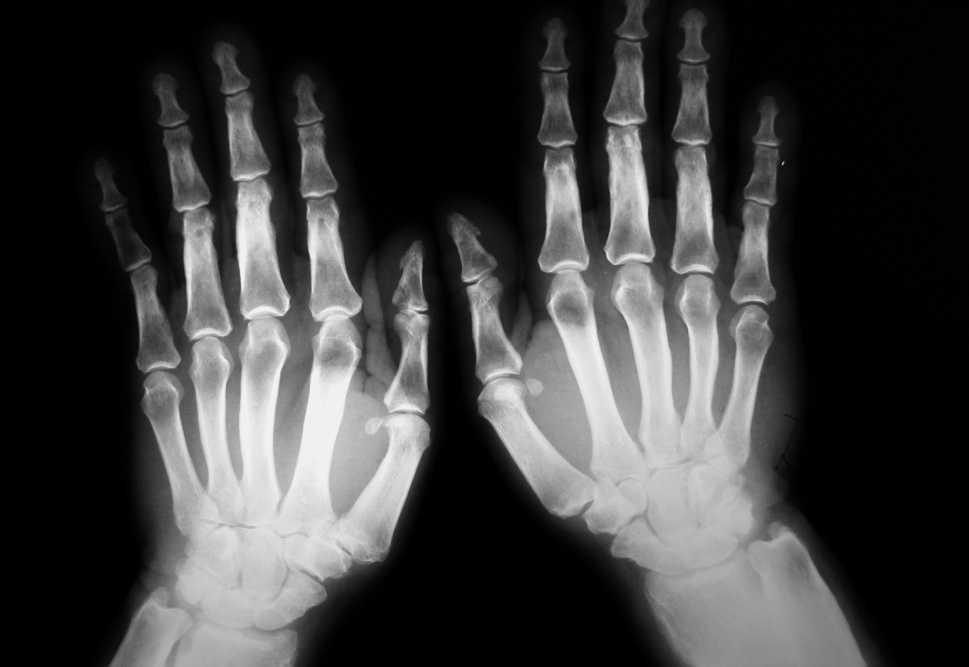

Se le realizó un estudio radiológico (radiografías de cráneo, huesos largos, columna, pelvis, manos y pies) hallándose una hiperostosis en los huesos de los antebrazos, el fémur y la tibia con una periostitis acusada y lesiones de fractura consolidada en la tibia y el peroné izquierdos. En las radiografías de manos se observó una tumefacción de partes blandas, sobre todo en falanges distales, una periostitis y una hiperostosis de los huesos metacarpianos y primeras falanges (fig. 1). En las radiografías de ambos pies también se apreció una hiperostosis de huesos metatarsianos, osteofitos y una esclerosis en el pie derecho.

Figura 1. Hiperostosis y periostitis en huesos metacarpianos y primeras falanges. Tumefacción de partes blandas.

La clínica reumatológica, como sucedió en nuestro caso, suele ser el motivo de consulta debido a dolores óseos, derrame articular y artritis asimétrica3. Al realizar un estudio radiográfico se observa osificación irregular periostótica afectando sobre todo a los huesos largos, metacarpo, metatarso, falanges y epífisis. Además, puede apreciarse un engrosamiento de los tejidos blandos, calcificaciones de las inserciones musculotendinosas y, raramente, erosiones articulares7. Requiere realizar el diagnóstico diferencial con la artritis psoriásica y la artritis reumatoide8.